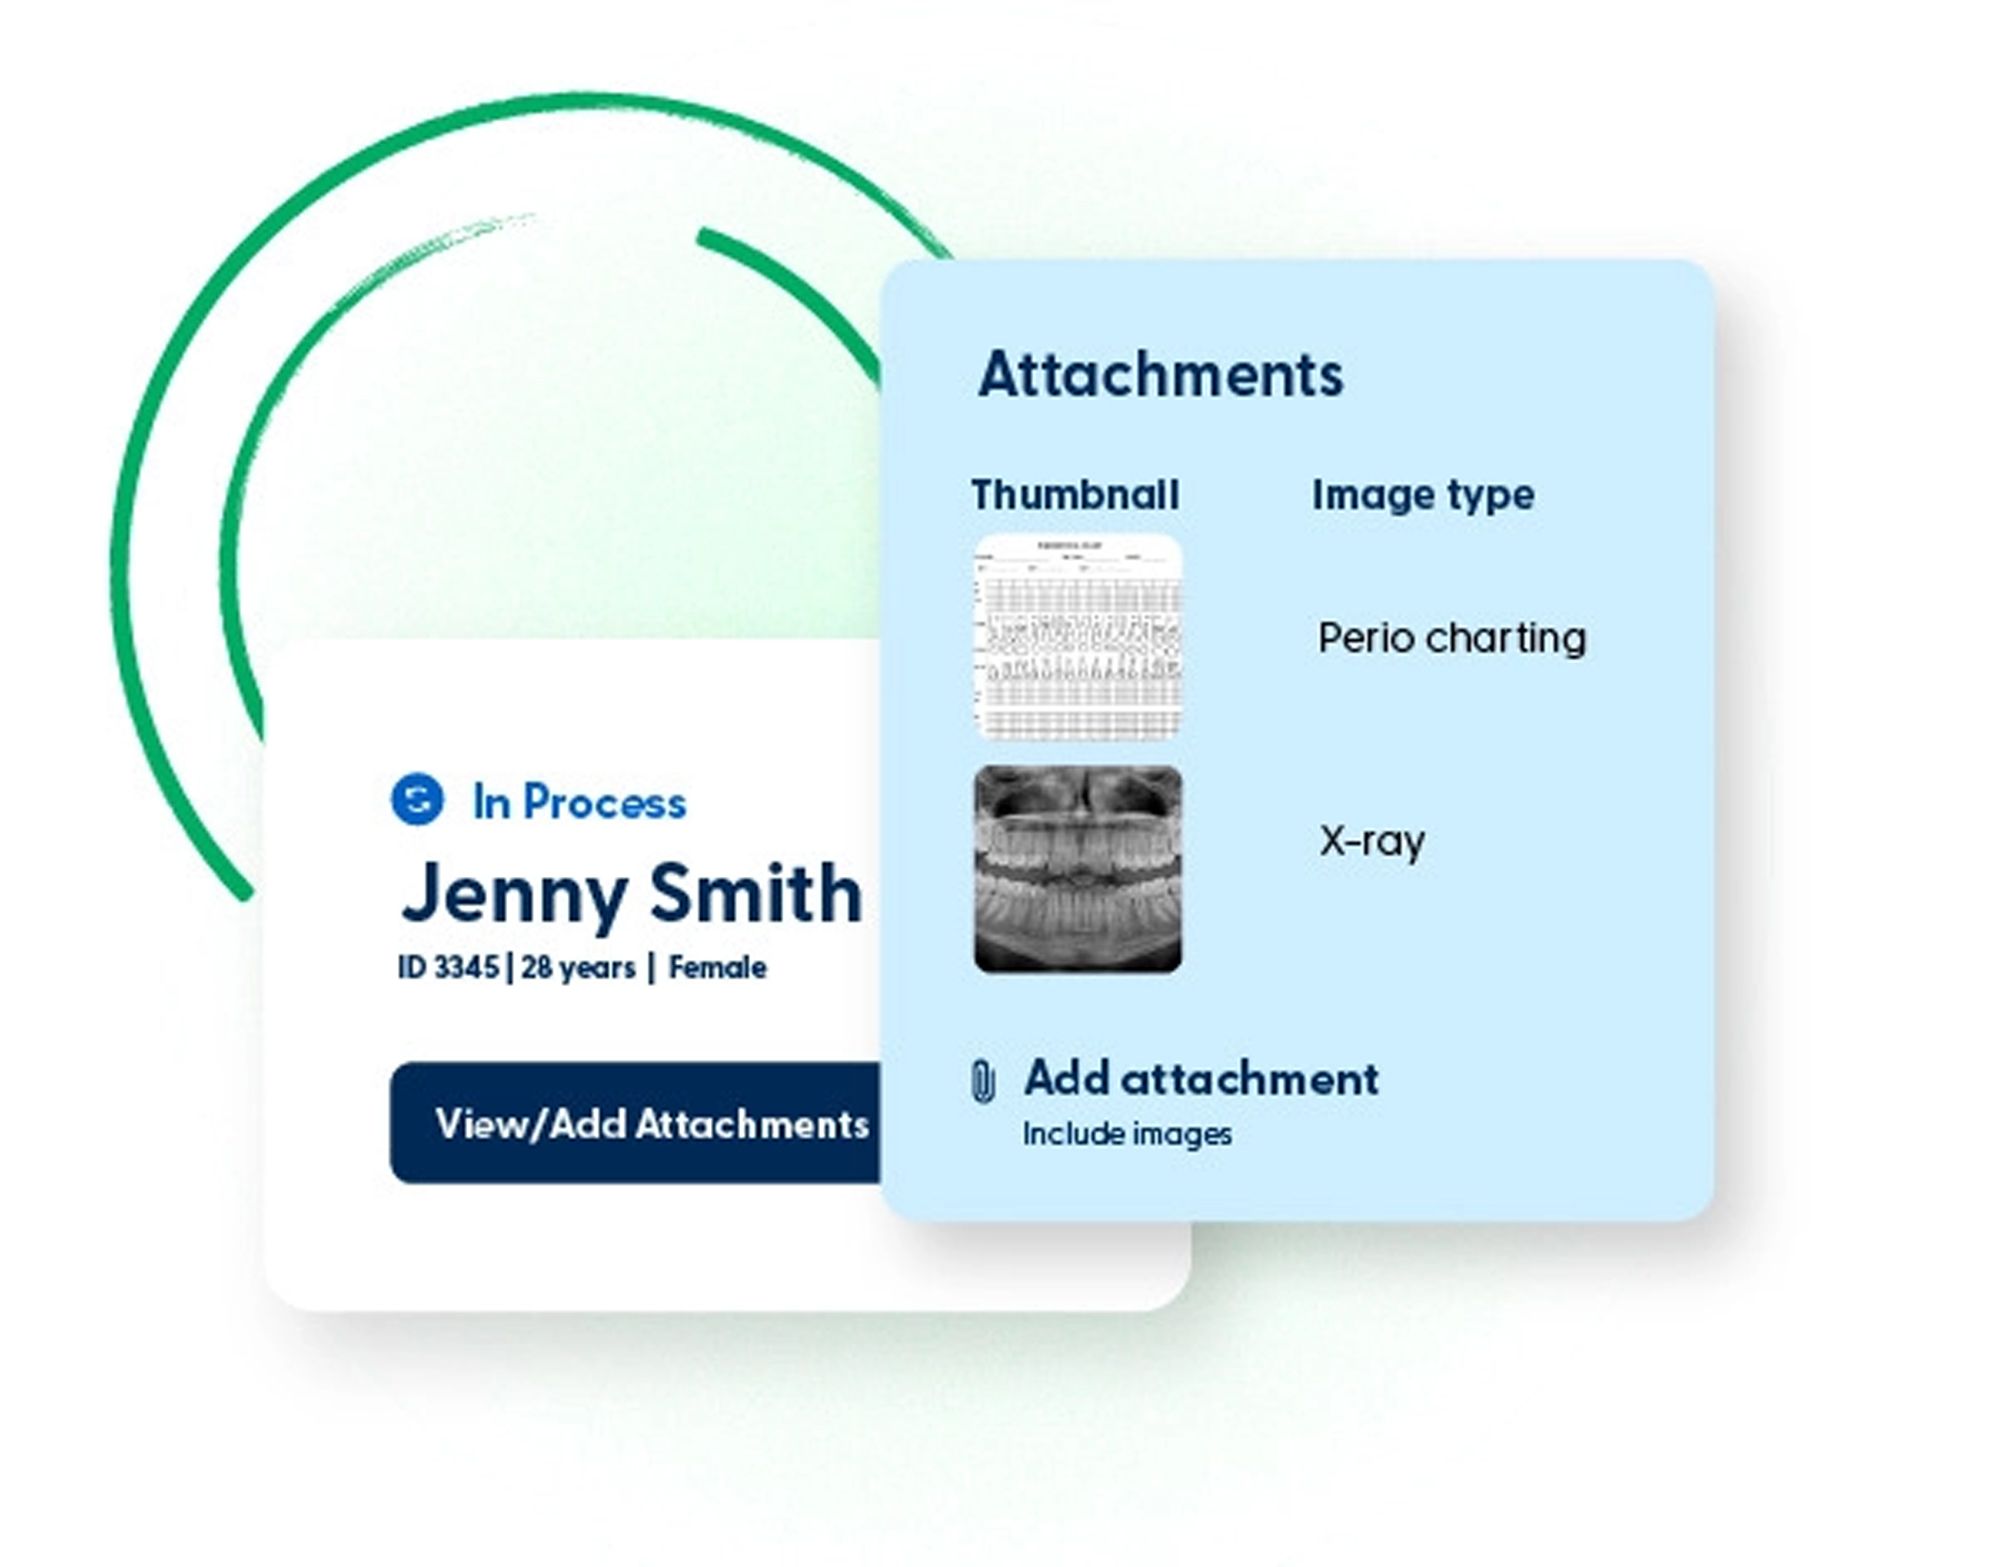

Planmeca Romexis® Smart are artificial intelligence (AI) tools for its Planmeca Romexis software platform. The feature allows the segmentation and recognition of anatomies, such as teeth, nerves, jaws, airways, and sinuses. This enables easier and faster use of the software and excellent visualization of the case for patient education. With the help of AI, CBCT images and intraoral scans are automatically mapped. Thanks to the automatic tooth number recognition, a CBCT volume can be easily navigated just by clicking on the tooth number in the tooth chart, and the software centers all views on the tooth of interest.